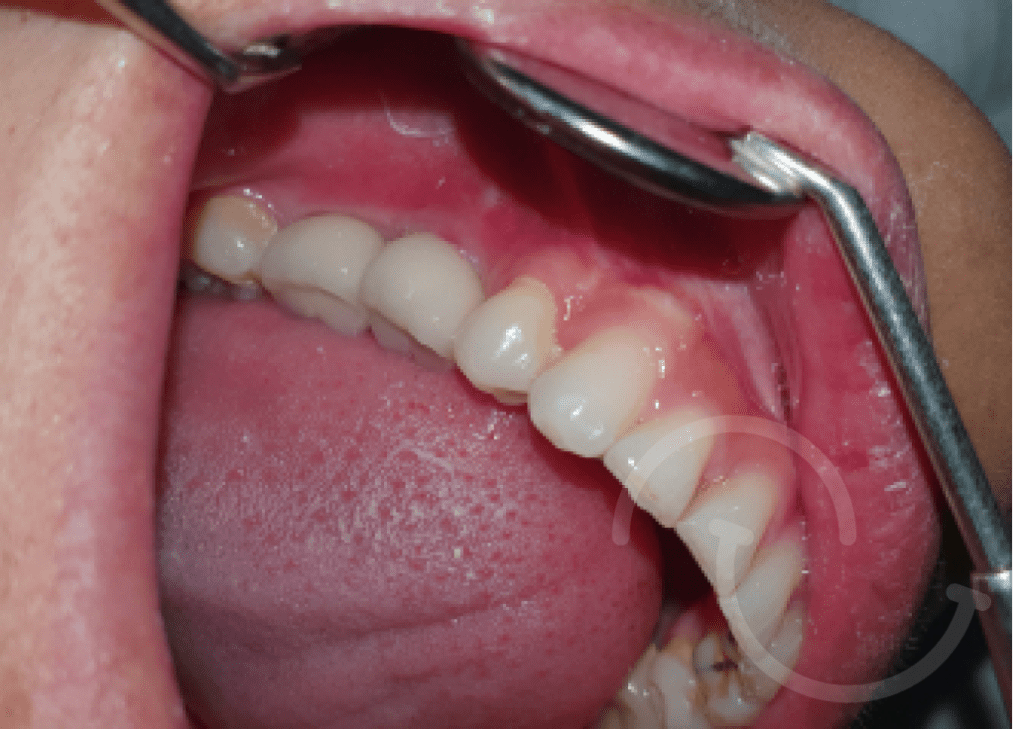

Injerto de mentón

Caso 1

Caso 2